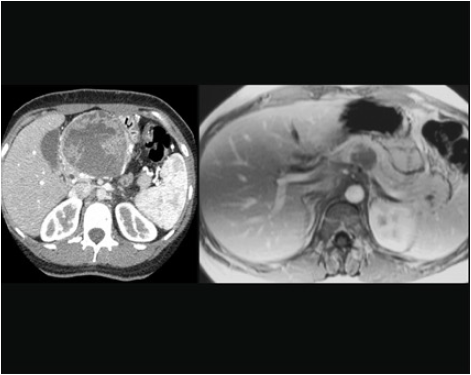

İnsülinoma şüphesi olan bir kişide endokrin uzmanlarınca yapılan bir dizi testten sonra aşırı insülin salgılandığı saptanırsa tümörün yerini saptamak için görüntüleme yöntemlerine başvurulur. Hastaların çoğunluğunda tümör 1, 5 cm’den küçük olduğu için standart görüntüleme yöntemleri yetersiz kalabilir. Endoskopik ultrasonografi tümörün yerini saptamada çok yararlı bir yöntemdir. İnsülinomaların %90’ı iyi huyludur ve cerrahi olarak çıkartıldıklarında tam tedavi olurlar.